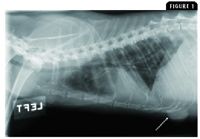

Common metastatic sites include the lungs (diffuse or nodular metastasis) (Figure 1) and regional lymph nodes, but metastases may also occur in the liver, spleen, brain, and bone.4-8,14-17 Regional lymph node metastasis is reported to be present in more than 25% of cats at diagnosis.4,12 At necropsy, 76% of cats have pulmonary metastasis and 40% have pleural metastasis,12 with up to 93% of cats having one or more sites of metastasis (lymph nodes, lungs, pleura, liver).18

Figure 1. A lateral thoracic radiograph of a female cat presenting for evaluation of inappetence, behavioral changes, and rapid breathing. Radiographic findings are consistent with diffuse pulmonary metastasis (diffuse infiltrates) from a relatively large (> 3 cm) primary mammary tumor (white arrow).